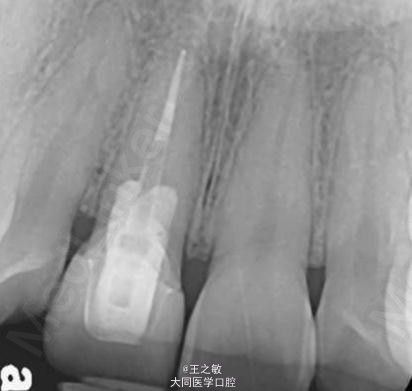

行牙龈移植术 处理:信封法撑开,根向深度5毫米,腭侧取结缔组织移植,把结缔组织当成信纸放入,使用可吸收线在近远中两侧做褥式缝合固定

治疗后三个月並以全瓷冠修复完成